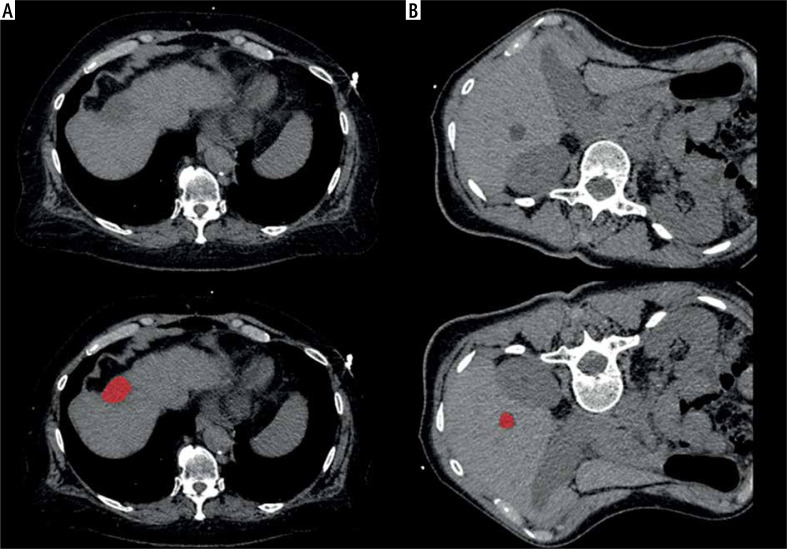

Abstract Image